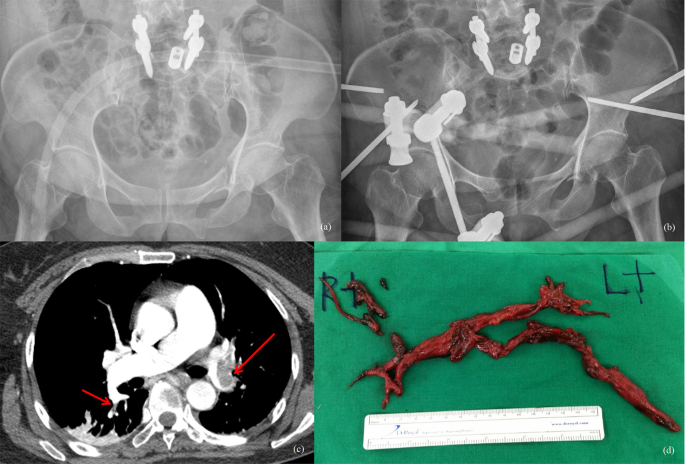

For treatment, either Enoxaparin or Dalteparin via subcutaneous injection at treatment dose was used for 5–7 days and oral medication (e.g. dabigatran) was continued for 3 months. In a single case of PE, an emergency thrombectomy was required. (Fig. 1).

A 52-year-old female patient with a left rami fracture and diastasis of the left SI joint after a traffic accident underwent general anaesthesia for pelvic ring stabilization (a). After general anaesthesia, the patient rapidly developed hypoxia and tachycardia and the operation was not performed. Only external fixation was performed (b). CT angiography was performed to confirm total occlusion of the left pulmonary artery and right segmental thrombus (red arrow) (c). Thrombectomy was immediately performed (d).